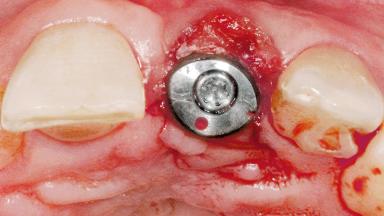

Late Flapless Placement of an Implant in a Maxillary Left Central Incisor Site

A 39-year-old male patient presented with a chief complaint of discomfort and gingival discoloration around his maxillary left central incisor. He was in good general health and was a non-smoker. His past dental history was significant because of the traumatic fracture of tooth 21 in a sporting accident at age 13. Initial dental treatment included endodontic therapy and a full-coverage restoration. The patient became symptomatic 5 years later, when structural failure of the tooth resulted in the dislodgment of the crown. Endodontic retreatment, apical surgery, and post-and-core restoration were performed.

Bone Augmentation Horizontal|Staged

Augmentation Materials Xenogenous|Membrane

Soft Tissue Grafting Simultaneous

Bone Volume Deficient horizontally, requiring prior grafting